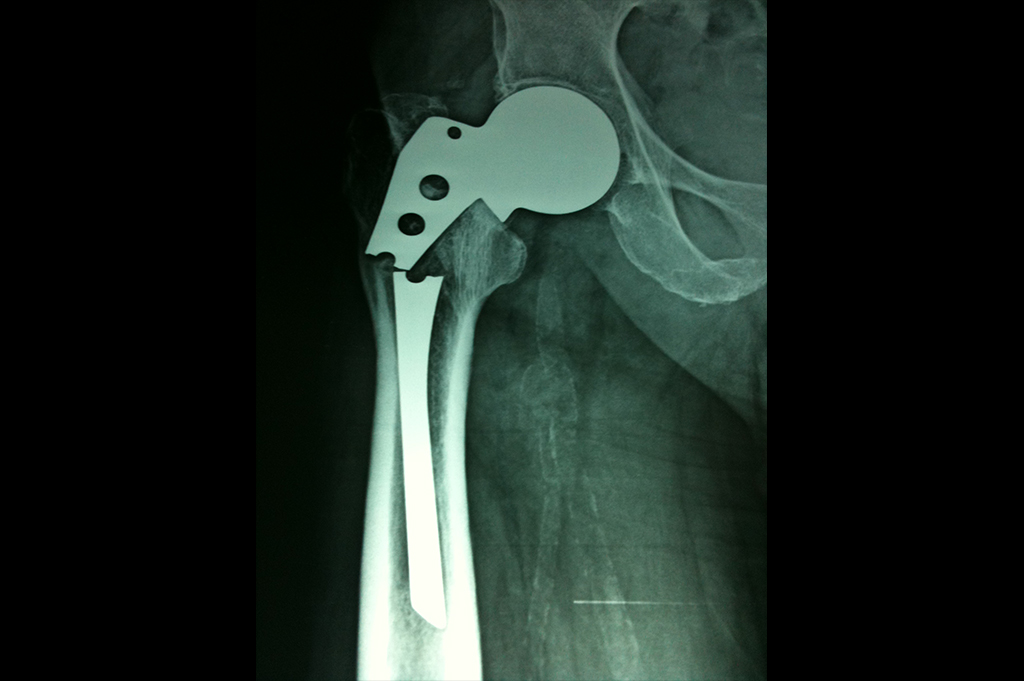

Periprosthetic Fracture THR

Total Hip Replacement - THR